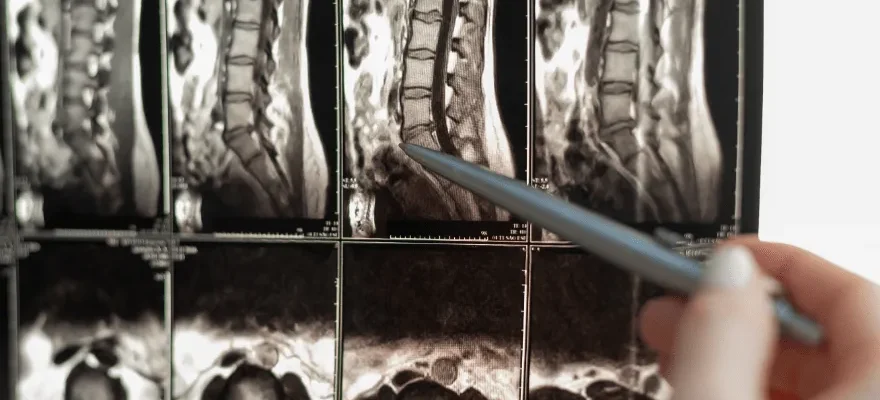

Lomber BT (Bilgisayarlı Tomografi), omurganın lomber (bel) bölgesinin detaylı görüntülerini almak için kullanılan bir görüntüleme tekniğidir. X-ışınları ve bilgisayar teknolojisi yardımıyla, kesit görüntüler elde edilerek doktorlar tarafından detaylı bir şekilde incelenir. Bu sayede, lomber bölgede meydana gelen anormallikler, hastalıklar veya yaralanmalar hakkında detaylı bilgi sahibi olunabilir.

Lomber BT çekimi hastanın radyoloji bölümünde yatarak gerçekleştirdiği bir işlemdir. Genellikle kontrast madde kullanılmadan önce, hastanın karın bölgesindeki tüm metal aksesuarlar çıkartılır. Daha sonra, BT makinesi etrafında dönerken, hastanın hareketsiz kalması gerekmektedir. Tüm işlem genellikle 10-30 dakika arasında sürmektedir. Çekim tamamlandığında, elde edilen görüntüler bir radyolog tarafından değerlendirilir.

Lomber BT sayesinde, bel bölgesinde yer alan omurlar, diskler, sinirler ve diğer yumuşak doku yapıları detaylı bir şekilde incelenebilir. Bel ağrısının nedenleri, disk hernileri, omurga tümörleri, enfeksiyonlar, omurilik daralması ve omurga deformiteleri gibi birçok farklı durum bu yöntemle teşhis edilebilir.